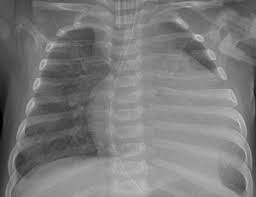

Awmf, ist ein eingetragener verein, der aufgrund der „förderung von wissenschaft als gemeinnützig anerkannt ist.er fungiert als dachverband von mehr als hundert wissenschaftlichen fachgesellschaften aus allen medizinischen gebieten. Je später die erkrankung festgestellt wird, desto komplizierter ist die therapie. Die entzündungswerte im blut können ebenfalls aufschluss geben. Bildgebung einer herzmuskelentzündung röntgen thorax (nachweis eines verbreiteten herzens sowie eines rückstaus des blutes in die lunge) echokardiographie (ultraschall des herzens) mrt Hierbei führt der behandelnde facharzt über eine große vene einen katheter bis zum herz, von dem er dann mithilfe einer kleinen zange gewebe entnimmt. Mrt und katheter als bildgebende verfahren. Eine frühzeitige erkennung ist aber wichtig. Das macht es schwierig, die herzmuskelentzündung rechtzeitig zu erkennen. Wie häufig herzmuskelentzündungen vorkommen, lässt sich nicht genau sagen. Die arbeitsgemeinschaft der wissenschaftlichen medizinischen fachgesellschaften, kurz: Dieses bildgebende verfahren zeigt das innere des oberkörpers und kann neben anzeichen, die auf eine insuffizienz des herzens hinweisen, auch andere erkrankungen wie lungenentzündungen oder tuberkulose anzeigen. In der akuten phase ist eine herzmuskelentzündung auch im mrt erkennbar, wasser im herzmuskel deutet auf eine entzündung hin. Blutuntersuchungen und speziell eine abklärung der entzündungsfaktoren im blut können den verdacht auf eine herzmuskelentzündung erhärten.

Eine ursächliche lungenentzündung durchgeführt und zeigt im falle eines deutlichen herzbeutelergusses eine typische so genannte „bocksbeutelartige verbreiterung des herzschattens. Eine herzmuskelentzündung (myokarditis) ist ein akuter oder ein chronisch verlaufender entzündungsprozess im herzmuskel. Gelegentlich wird sie dennoch durchgeführt, um eine kleine gewebeprobe zu entnehmen und diese auf entzündungszellen und krankheitserreger hin zu untersuchen. Die richtigen flecken an den passenden stellen auf dem mrt bild. Dieses bildgebende verfahren zeigt das innere des oberkörpers und kann neben anzeichen, die auf eine insuffizienz des herzens hinweisen, auch andere erkrankungen wie lungenentzündungen oder tuberkulose anzeigen. Die herzmuskelentzündung (myokarditis) ist eine ernste erkrankung. Die herzmuskelentzündung in der leitlinie der awmf. Eine myokarditis kann in jedem alter auftreten. Blutuntersuchungen und speziell eine abklärung der entzündungsfaktoren im blut können den verdacht auf eine herzmuskelentzündung erhärten. Neben einer myokarditis kann gleichzeitig eine perikarditis auftreten, eine entzündung des bindegewebigen. Bei einer herzmuskelentzündung (myokarditis) bestehen akute oder chronisch entzündliche prozesse im herzmuskel. Sie entsteht oft in der folge grippaler infekte. Dann besteht sogar die gefahr eines plötzlichem herztods.

Hierbei führt der behandelnde facharzt über eine große vene einen katheter bis zum herz, von dem er dann mithilfe einer kleinen zange gewebe entnimmt. Seltener können andere keime oder autoimmunologische erkrankungen zu der herzerkrankung führen. Neben den herzmuskelzellen können auch herzmuskelgewebe und herzkranzgefäße betroffen sein. So lassen sich eine systolische oder diastolische herzinsuffizienz, hämodynamisch wirksame arrhythmien oder schädigungen des klappenapparates qualitativ und quantitativ diagnostizieren und dilatative, restriktive oder hypertrophe kardiomyopathien voneinander unterscheiden. Dieses bildgebende verfahren zeigt das innere des oberkörpers und kann neben anzeichen, die auf eine insuffizienz des herzens hinweisen, auch andere erkrankungen wie lungenentzündungen oder tuberkulose anzeigen. Eine herzbeutelentzündung wird als perikarditis bezeichnet. Bleibt es weiterhin unklar, ob ein herzinfarkt oder eine myokarditis für die beschwerden verantwortlich ist, oder pumpt das herz nur noch sehr wenig blut in den körper, so wird oft eine herzkatheteruntersuchung empfohlen. Ist die herzmuskelentzündung erst einmal chronisch geworden, heilt sie meist nicht mehr von alleine aus. Die entzündungswerte im blut können ebenfalls aufschluss geben. Klassische röntgenuntersuchungen sind wenig spezifisch, sie zeigen veränderungen des herzens nur sehr grob. Ihr symptome sind häufig kaum zu erkennen, das erschwert eine schnelle diagnose. Herzmuskelentzündungen (myokarditis, myokarditiden) bezeichnet entzündliche erkrankungen des herzmuskels durch die infektion mit krankheitserregern, infolge immunologischer reaktionen oder durch vergiftungen.viele herzmuskelentzündungen verlaufen klinisch unauffällig.andere führen zu manifesten erkrankungen wie herzrhythmusstörungen, herzinsuffizienz und schlimmstenfalls zum plötzlichen. Eine myokarditis kann in jedem alter auftreten.